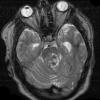

VASCULAR

Cavernous Angioma (9)